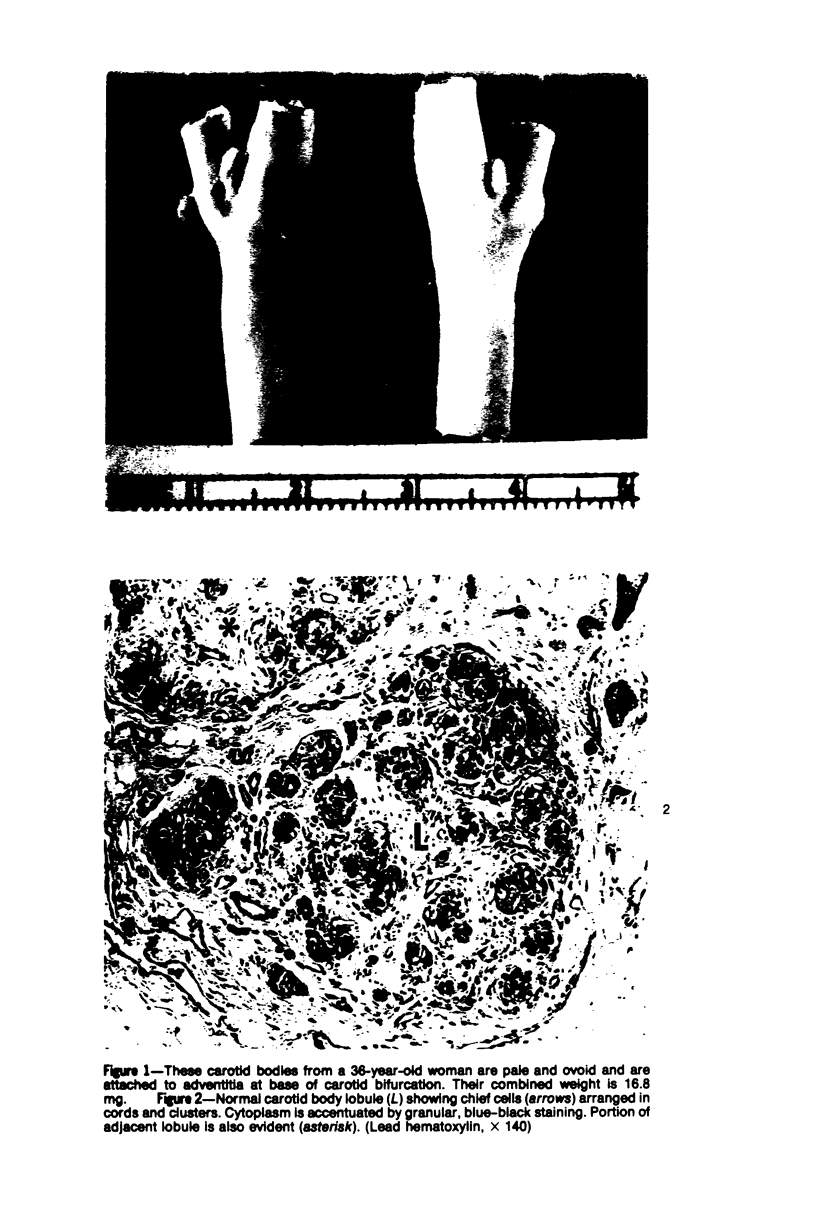

Vagal and carotid body paraganglia were obtained from 43 randomly selected autopsies performed at the National Naval Medical Center. In each case, tissue from both sides was step sectioned and comparatively studied. The mean combined weight of carotid bodies in 37 control patients was 25.9 mg. There was good correlation between size and number of separate paraganglia comprising the vagal body (seven left, six right). Lobules were closely related to the ganglion nodosum and were actually within it in three instances. Tissue resembling parathyroid was encountered within 4 of the 86 resected vagus nerves. Lymphocytic infiltration occurred in carotid and vagal body paraganglia of 28% and 16% of patients, respectively. There was Schwann cell proliferatation in carotid body lobules of 2 patients; in another patient, talc emboli were present. The mean combined weight of carotid bodies in 6 patients with chronic hypoxemia was 47.6 mg, significantly greater than in the control group; in each case, lobules were enlarged. Chief cell hyperplasia occurred in vagal body paraganglia of 2 patients; in two other patients, lobules were large with equal proliferation of constituent cells. These morphologic findings indicate that in patients with chronic hypoxemia some vagal body paraganglia can be ascribed a chemoreceptor role similar to but probably less important than that of the carotid body.